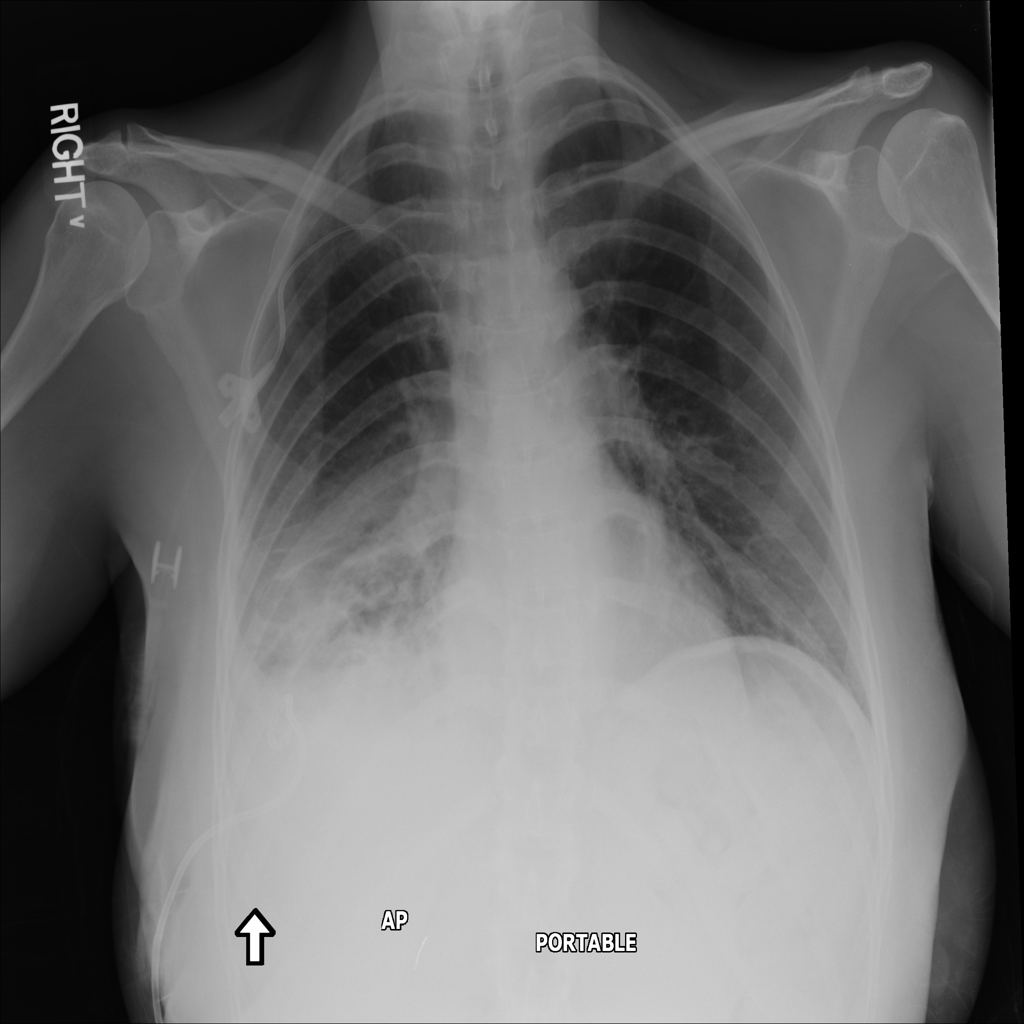

PAT-C0E5 · IMG-015Pneumonia

PAT-C0E5 · IMG-015

AP